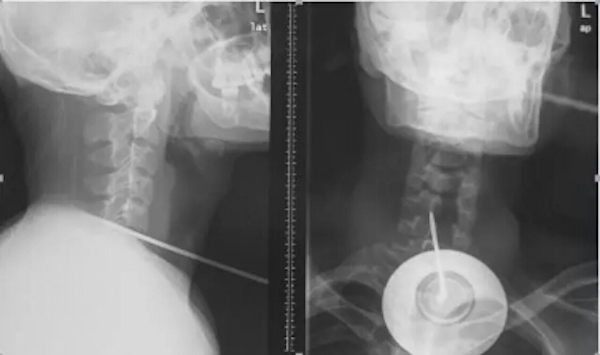

术前颈椎正侧位X线

2月13日凌晨3时,长征医院上演了一场真实版的“生死时速”。 一根长约17cm的钢针从患者颈部正中穿入气管、食管,通过椎体,贯穿脊髓,直达后路椎板穿出,生命危在旦夕。海军军医大学长征医院多科专家联手合作,紧急手术,展开了一场惊心动魄的生死大援救,成功拔出了夺命钢针。术后第二天,患者瘫痪的右侧上下肢功能明显恢复。

凌晨2时,脊柱二科主任史建刚教授接到会诊电话后,连夜从家里赶到医院。经查,患者钢针从颈部插入,贯穿气管、食管、椎体、脊髓,直达后路椎板,患者右侧上下肢无法动弹。医生迅速对病人的情况作出判断——病人属于严重综合性颈椎脊髓外伤,需要多科室联合救治。